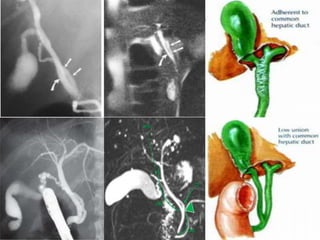

Cystic Duct

The gallbladder is attached to the common bile duct (CBD) via the cystic

duct, which is usually 2 to 4 cm long and contains tortuous folds, the

spiral valves of Heister . Diameter 2-3 mm.

The cystic duct usually joins the common hepatic duct (CHD) from the

right lateral aspect approximately halfway between the porta hepatis

and the ampulla of Vater to form the CBD.

The point at which the cystic duct joins the CHD is variable, from high in

the upper extrahepatic bile duct or one of the intrahepatic ducts (more

often the right) to low at the ampulla.

The cystic duct usually runs parallel to the CHD at least for a short

distance and may insert either anteriorly or posteriorly or spiral around

to insert on the medial aspect.